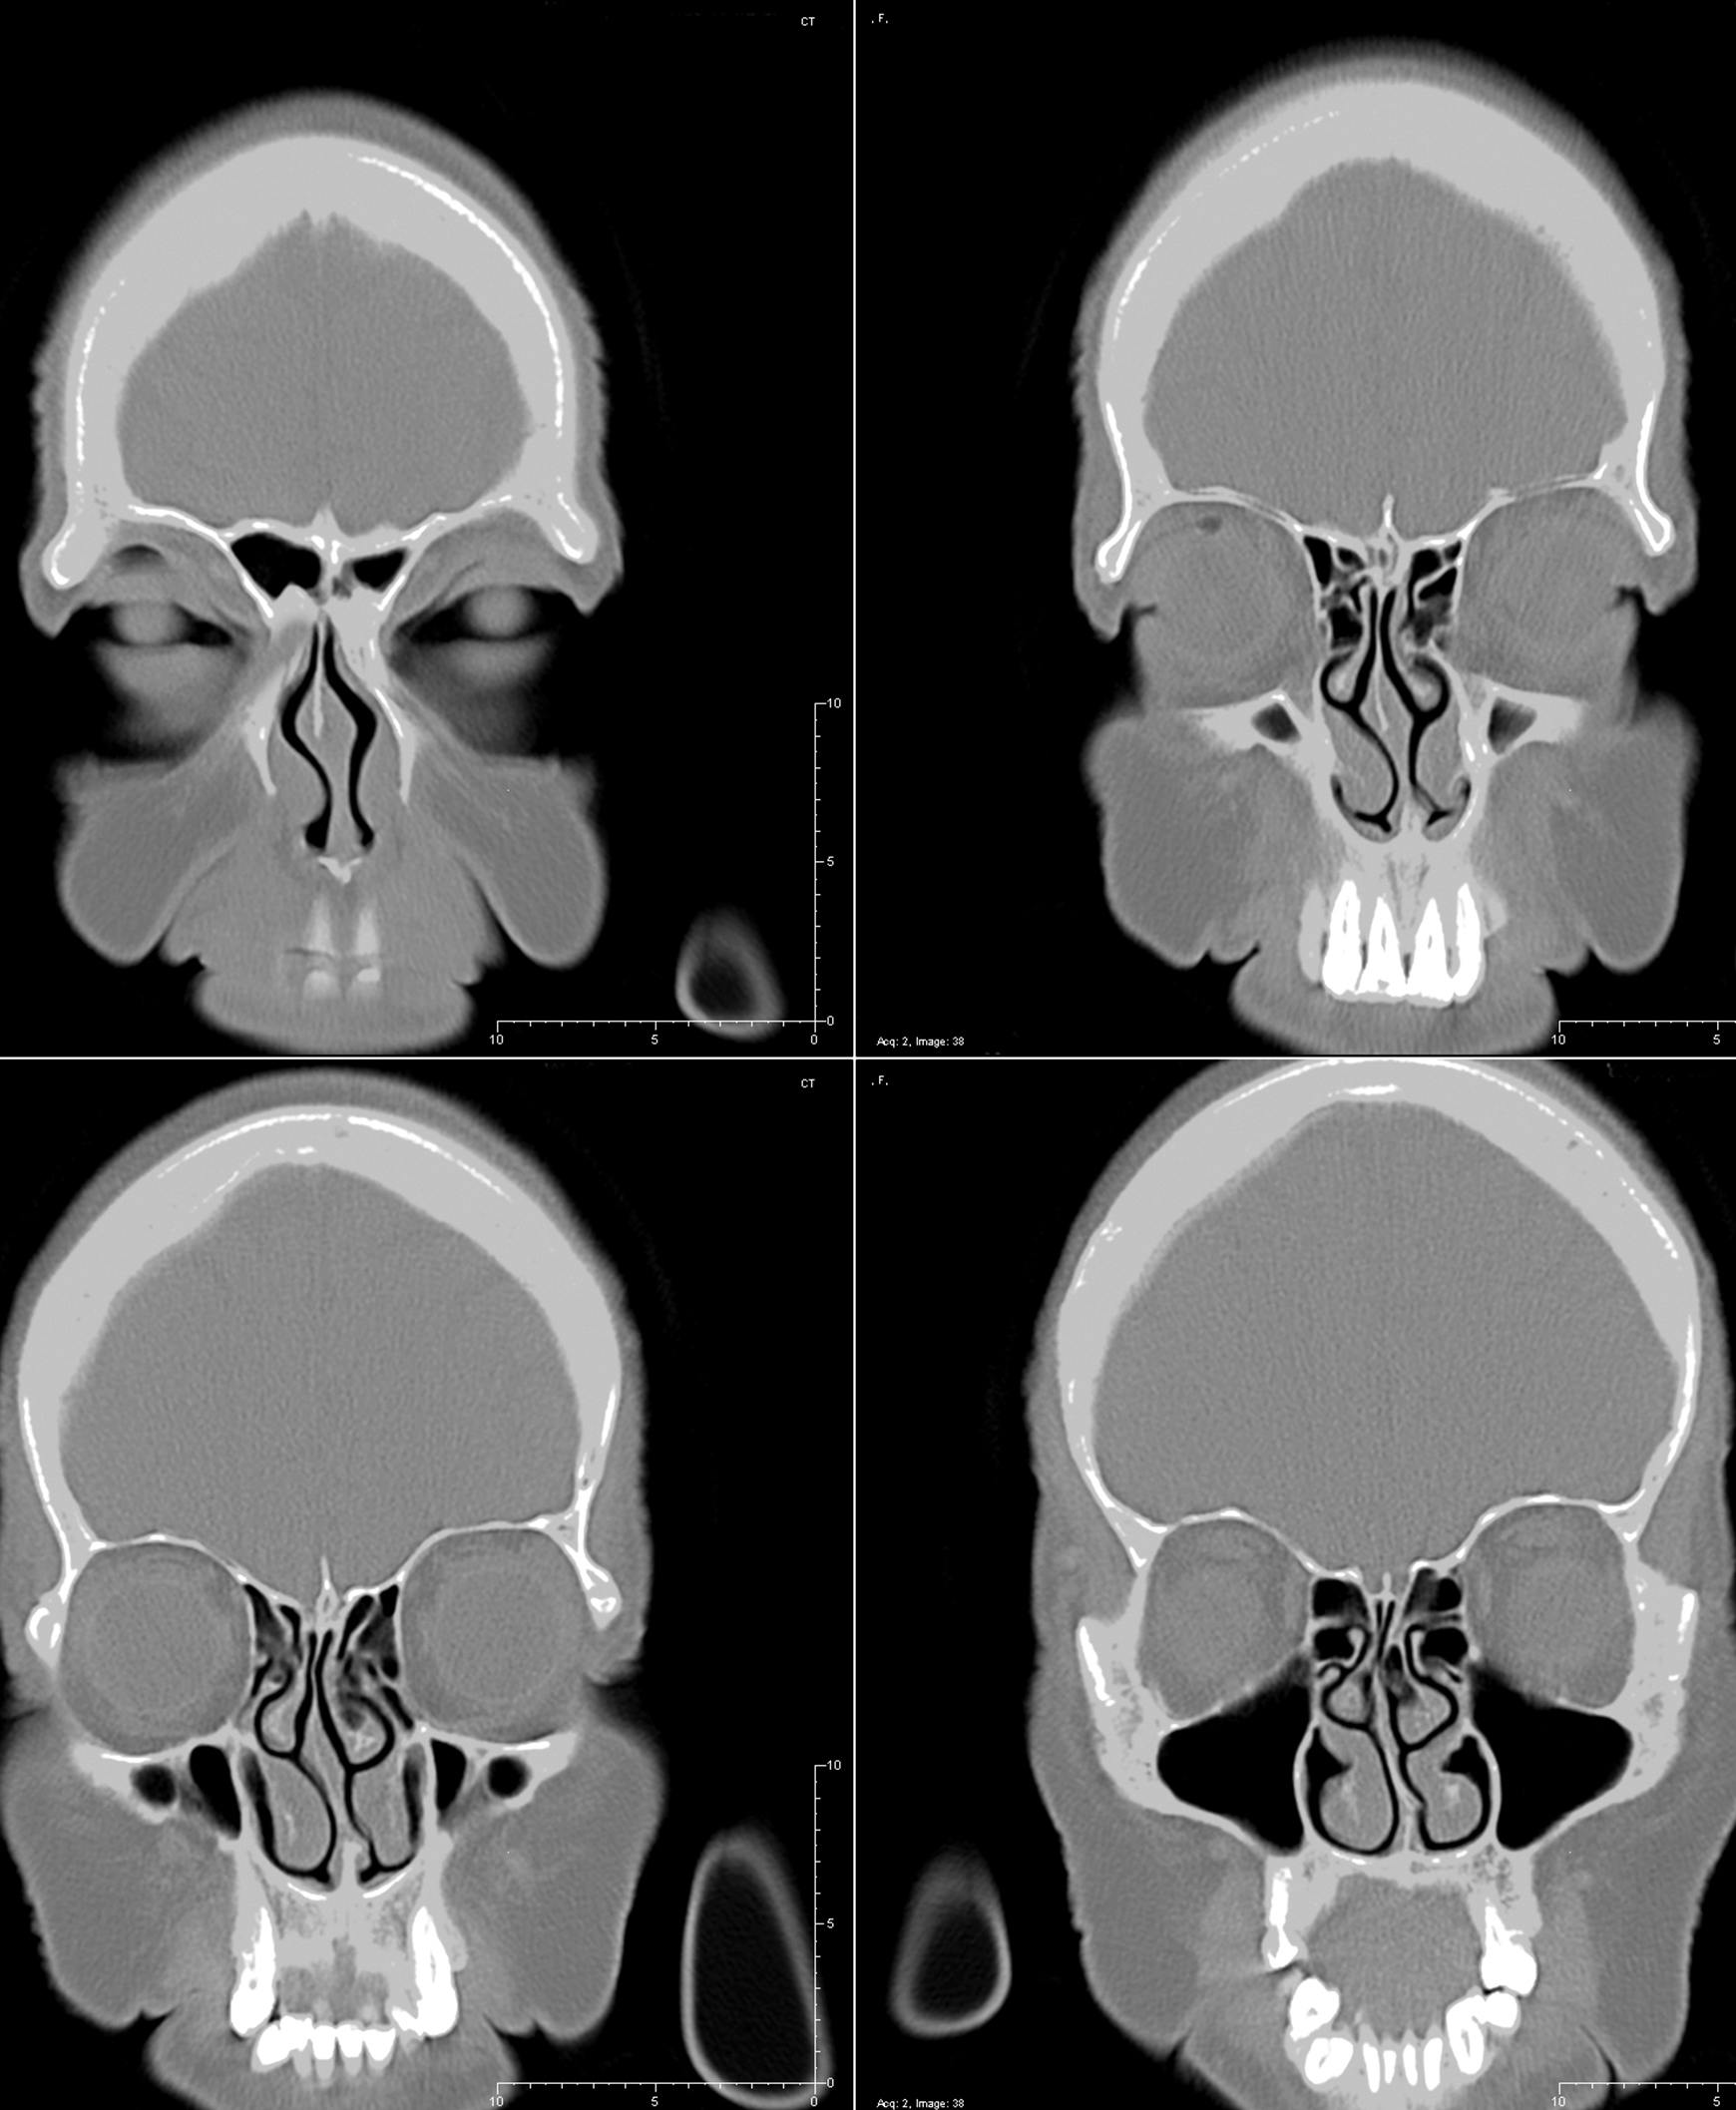

Sinus surgery is most often performed with the patient under general anesthesia. The procedure usually lasts 1-3 hours. It is performed through the nose with an endoscope: a tool that is something like a flexible telescope with a camera at the end. Dr. Reitzen uses this endoscope to see inside the nose so that she can widen the walls of the nasal passages and safely remove the cause of the blockage. The most common surgical tool that is used to reduce blockages is a microdebrider.